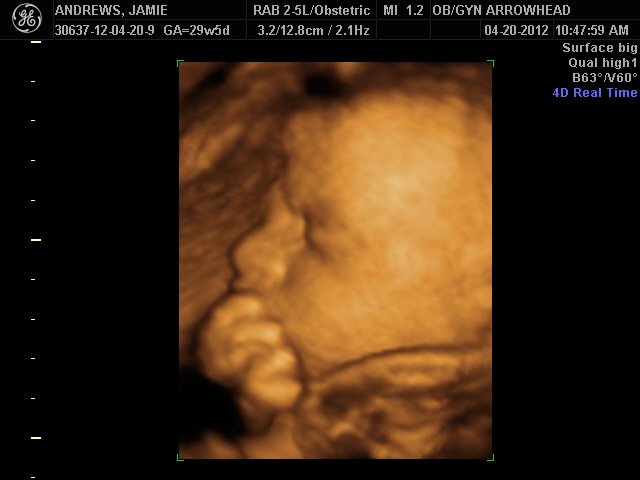

We offer complimentary 3D/4D Ultrasounds to all our OB patients around 30 weeks! The following photos are some examples of our work, shown with permission from our patients.